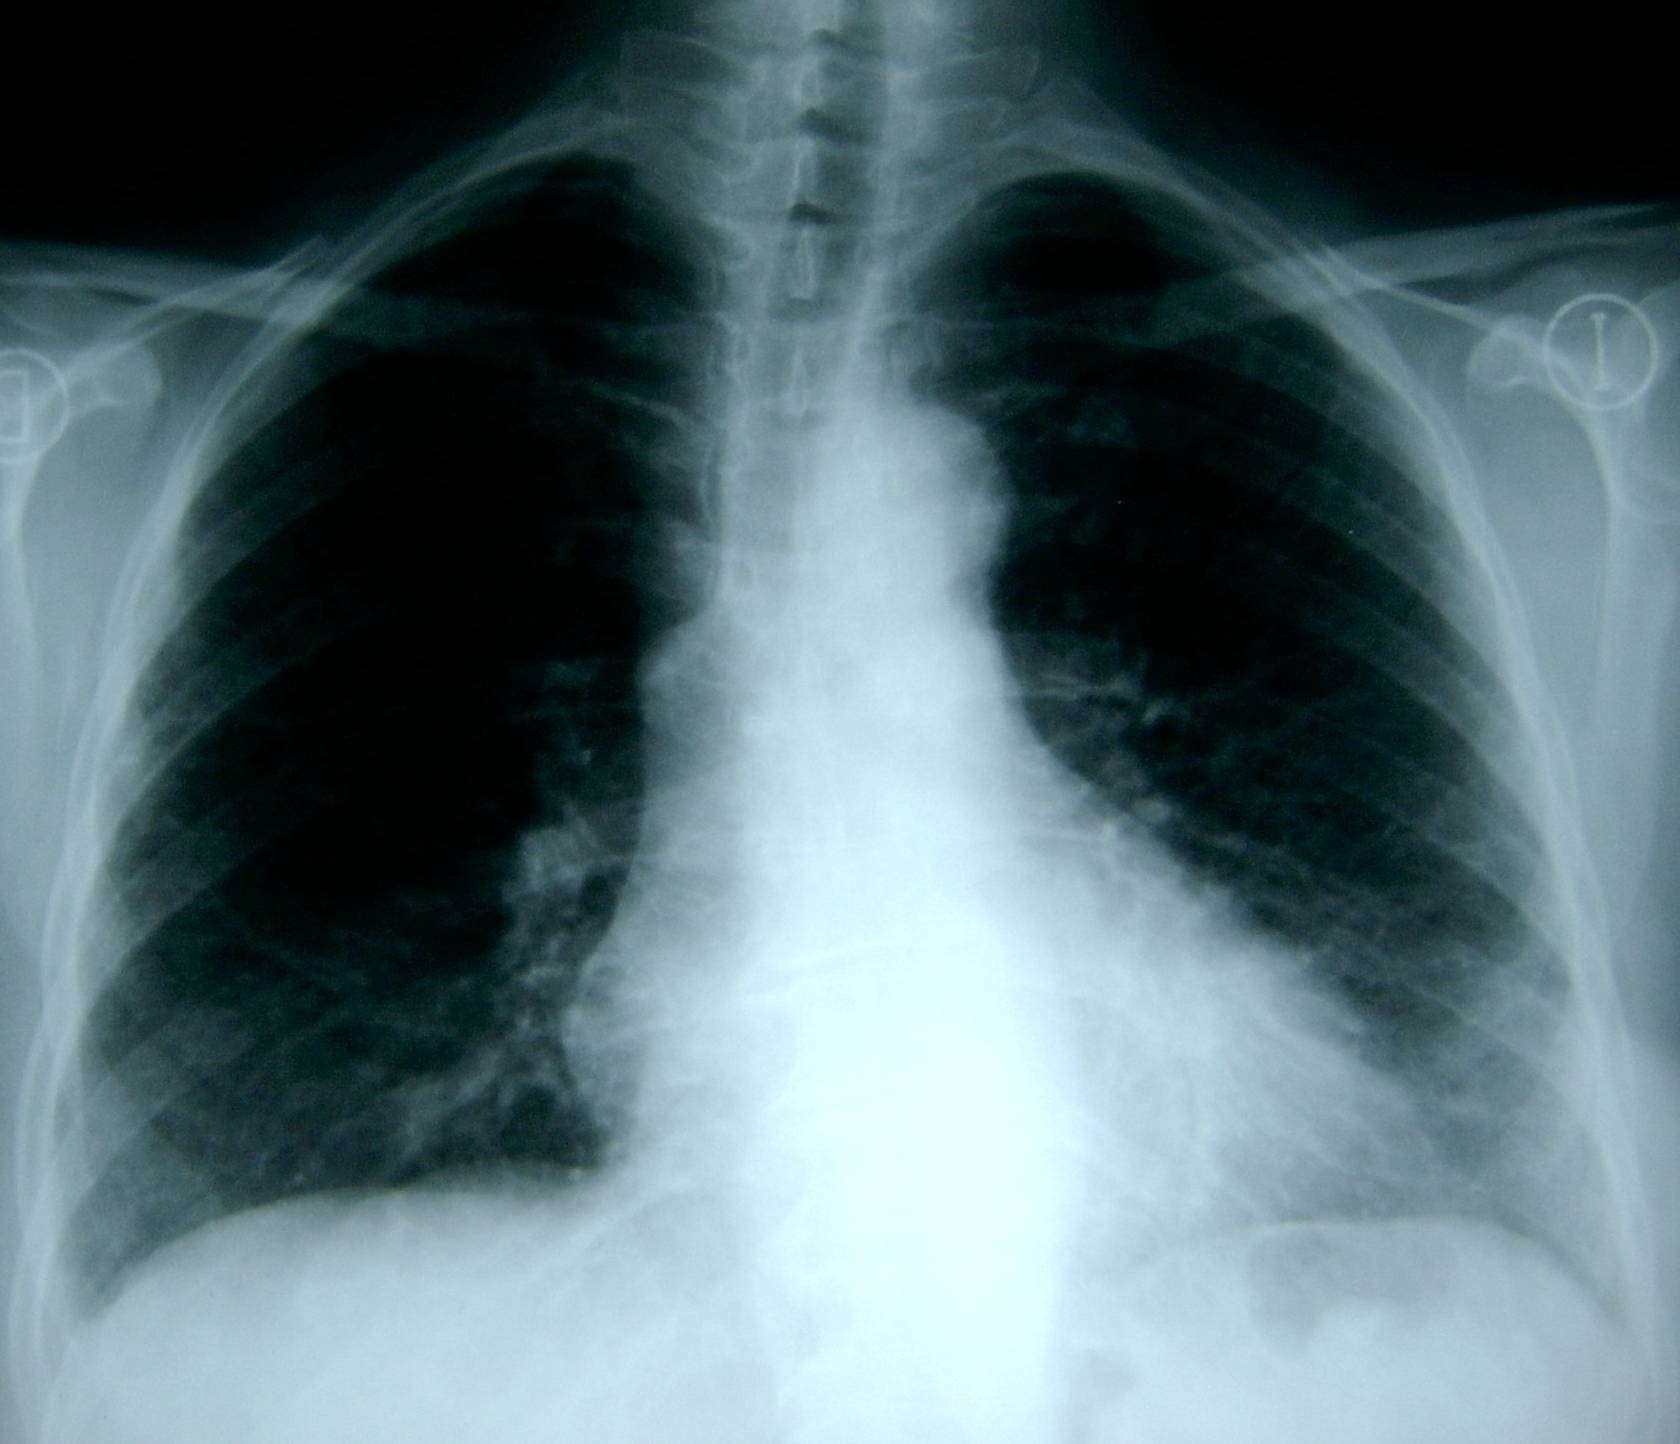

Поражение легких является одним из основных симптомов коронавируса (COVID-19). В данной статье представлены фото рентгеновских снимков, которые позволяют визуально оценить состояние легких при этом заболевании.

Фото рентгеновских снимков поражения легких при COVID-19

На фотографиях рентгеновских снимков видно, как вирус воздействует на легочную ткань. Характерные признаки поражения легких включают пятна, инфильтраты и наличие жидкости внутри легочных альвеол.

Фото рентгеновских снимков помогают врачам и специалистам визуально определить степень поражения легких и принять соответствующие меры лечения и поддержки пациента.